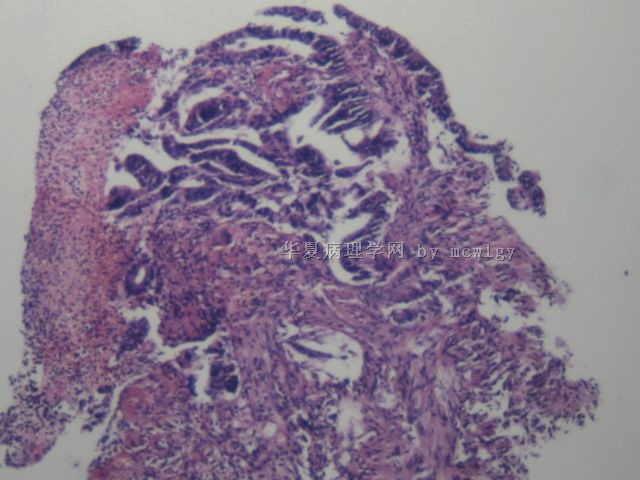

直肠黏膜胃镜取

姓    名: ××× 性别: 女  年龄:  64

• 直肠黏膜胃镜取图1

图1

×参考诊断

腺癌

见笑了?片子不好?太简单了直肠腺癌

粘膜肌侵犯,够腺癌了。

腺癌够了。